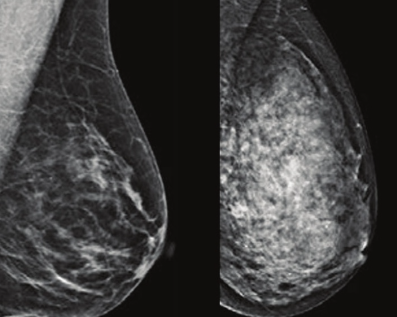

بافت پستان از غدد تولید کننده شیرو مجاری شیری تشکیل شده است. مجاری باریک موجود در پستان، شیر را از غدد تولید کننده شیر به نوک پستان می رسانند. بافتهای اطراف غدد شیری و نوک پستان باعث شکل دادن به پستان می شوند. بافتهای اطراف غدد و نوک پستان از مواد چربی و الیافی تشکیل شده اند. بیشتر از مواد چربی در پستان مواد فیبری وجود دارد که باعث تراکم بافت پستان میشود. تراکم پستان بر اساس اندازه پستان یا شکل آن و یا حس کردن آن نیست، فقط از طریق تصویر برداری قابل دیدن است. بافت چربی در ماموگرافی تیره بنظر می رسد در حالیکه بافت متراکم شده سفت و سفید است. رادیولوژیستی که ماموگرافی را مورد تجزیه و تحلیل قرار میدهد، اندازه و نسبت بافت چربی متراکم نشده و متراکم شده را تعیین و درجه تراکم پستان را تعیین می کند.

تجزیه و تحلیل تراکم بافت پستان در ارتباط با خطر سرطان پستان با چند روش مورد بحث قرار می گیرد. اولا، خواندن ماموگرافی از بافت پستانی که متراکم است مشکل تر است. و این به این علت است که نقاط متراکم، سفید شده و می تواند غدّه سرطانی را پنهان کند و به رنگ سفید در مامو گرافی دیده شود. این مورد به عنوان نتیجه یا اثر پنهانی نامیده می شود. به علت این اشتباه، زنانی که پستان متراکم داشته اند، غدّه پنهان شده آنها قابل دیدن نبوده است. ثانیا، تراکم پستان یک خطر مطلق برای سرطان پستان است. خطر سرطان برای زنان با پستان بسیار متراکم به اندازه پنج برابر بیشتر از زنانی است که دارای پستان با بافت چربی هستند. گرچه تراکم پستان با بالا رفتن سن کمتر می شود، ولی مطالعات تحقیقی هنوز نشان میدهد که با بالا رفتن تراکم پستان ، خطر سرطان هم اضافه می شود و سرطان به غدد شیری و نوک پستان هم منتقل می شود. این نوع سرطان پستان، سرطان پیشرفته نامیده میشود که در زنان ۶۵ ساله یا مسن تر اتفاق می افتد.